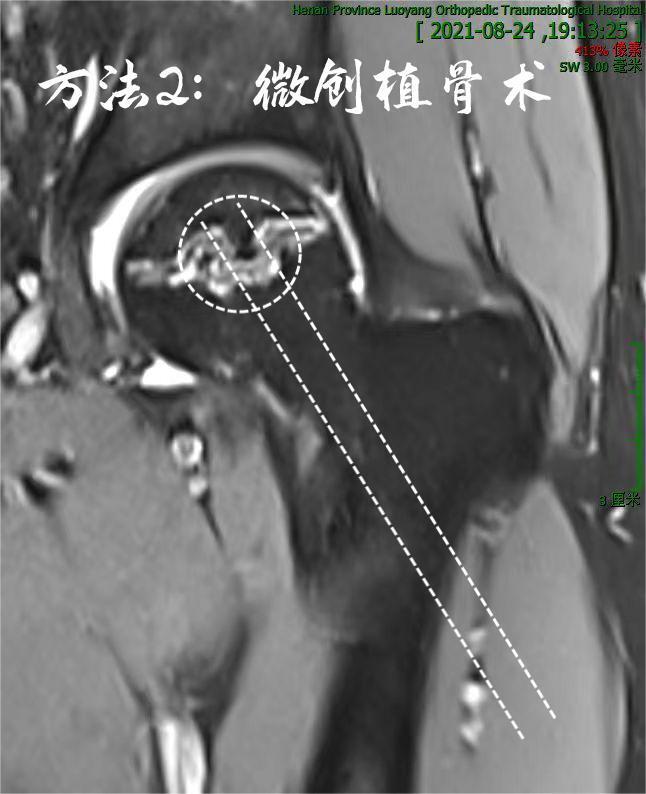

2. 也可以行微创减压植骨术,刀口约2cm,术后6天可出院: